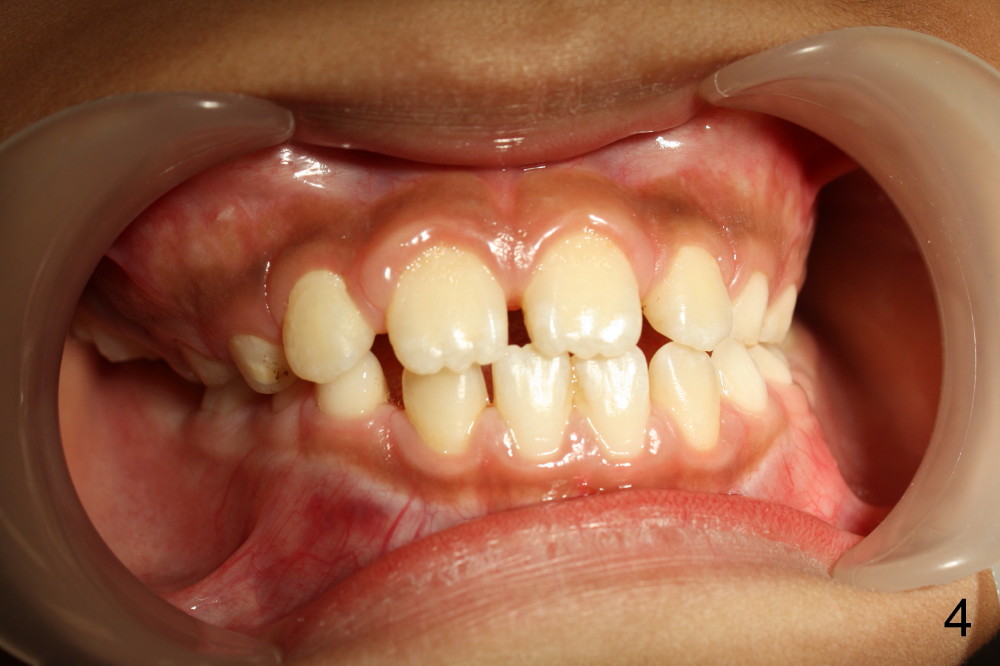

A 10 year 5 month old Chinese boy has no history of trauma. His mother reports that he sleeps on the right side of the mandible. He always rests his right mandible on the table when he is reading.

It appears that the chin deviates to the left (Fig.1). The lower dental midline also deviates (Fig.2,4). Profile shows possible bimaxillary protrusion (Fig.3). There is cross bite (deep overjet?) on the right side of the first permanent molars (Fig.5 mirror image), whereas the left posteriors apparently present edge-to-edge occlusion (Fig.6). Fig.7,8 are mirror views of the upper and lower arches, respectively. Panoramic X-ray demonstrates elongation of the right condyle (Fig.9). The right ramus appears to be longer than the left.